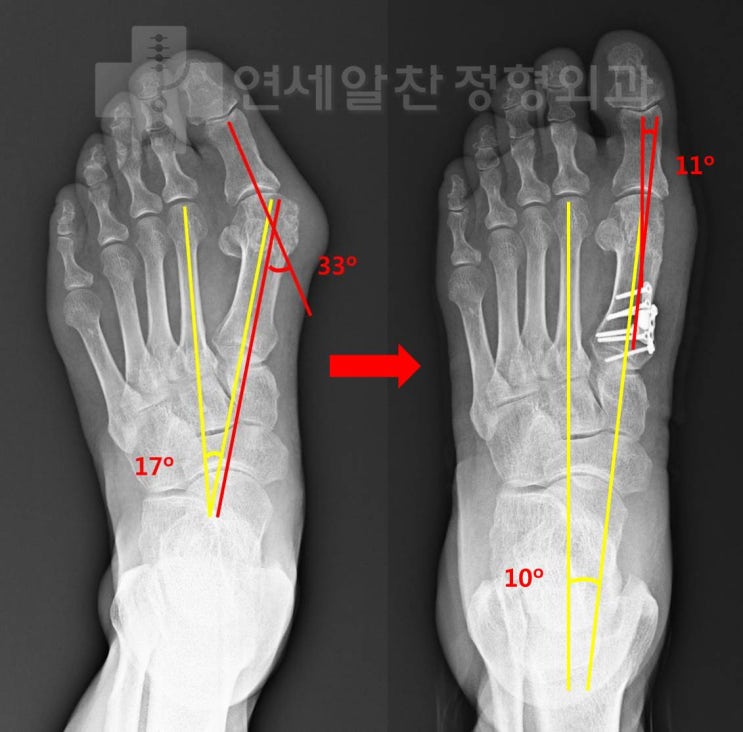

무지외반증에서 근위절골술을 이용한 교정절골술의 결과

71세 남자 환자로 좌측 발 통증을 주소로 내원하였다. 환자는 수차례의 스테로이드 주사를 맞았으며 최근 ...